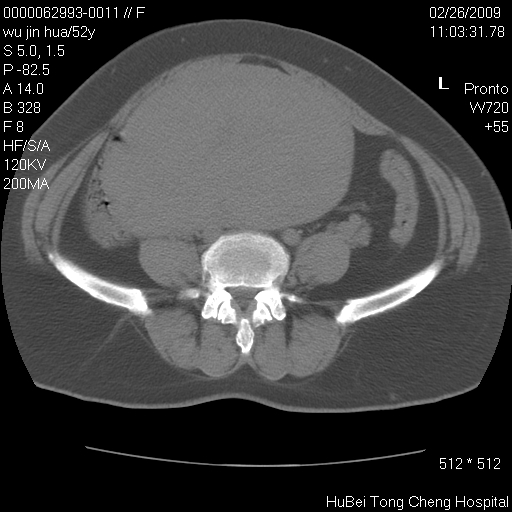

依据平片“腰椎退行性改变”报告,作椎间盘ct扫描时发现:

盆腔彩超报告:子宫肌瘤。(或许也漏诊了!)

影像表现:盆腹腔巨大占位,内密度均匀,边界清,未做强化。

来源:考虑来源于腹膜后肿瘤。

性质:以肉瘤可能性大。